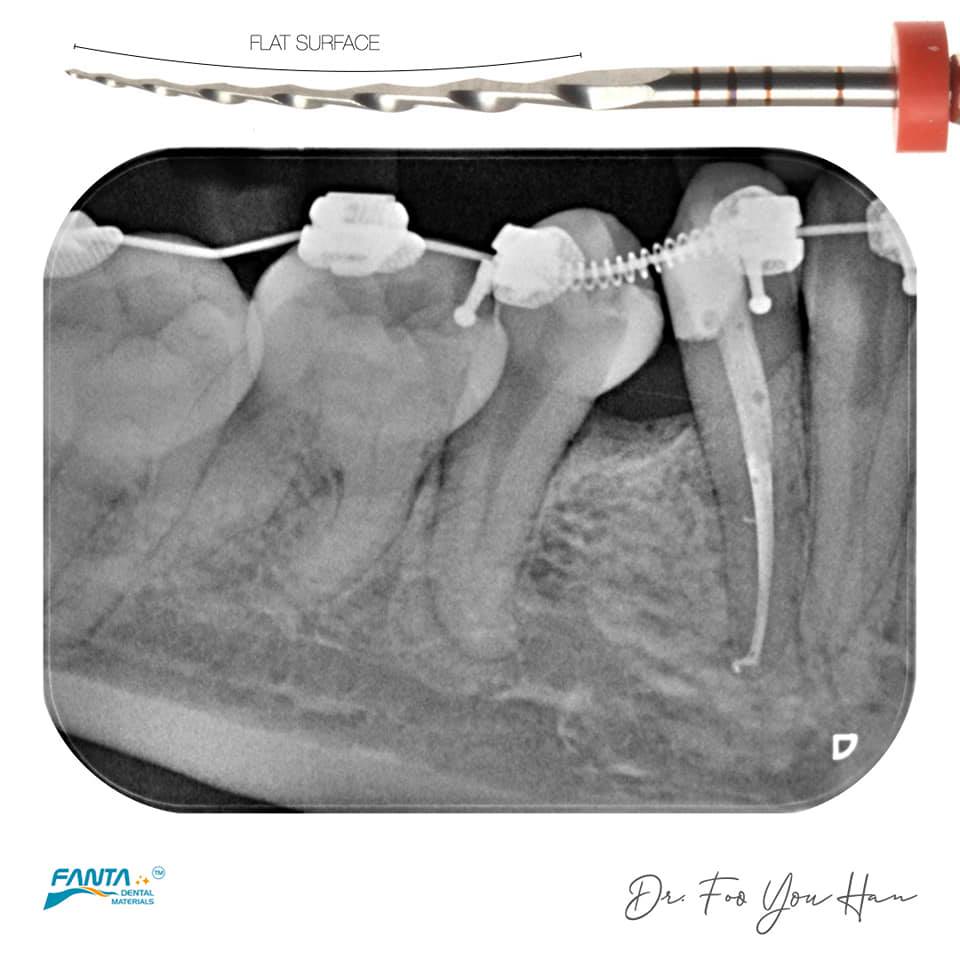

AFFOne

由于牙齿拥挤导致牙齿腐烂,导致不可逆的牙髓炎。分两次进行患者的根管治疗。由于根管在根尖处弯曲。在使用旋转锉之前,首先使用手用锉探查根管。由于牙齿钙化,使用Fanta的AF F-One进行根管预备,具有非常好的清理成型效果。这是我用于牙髓治疗的主要工具之一。

来自Dr. Foo You Han